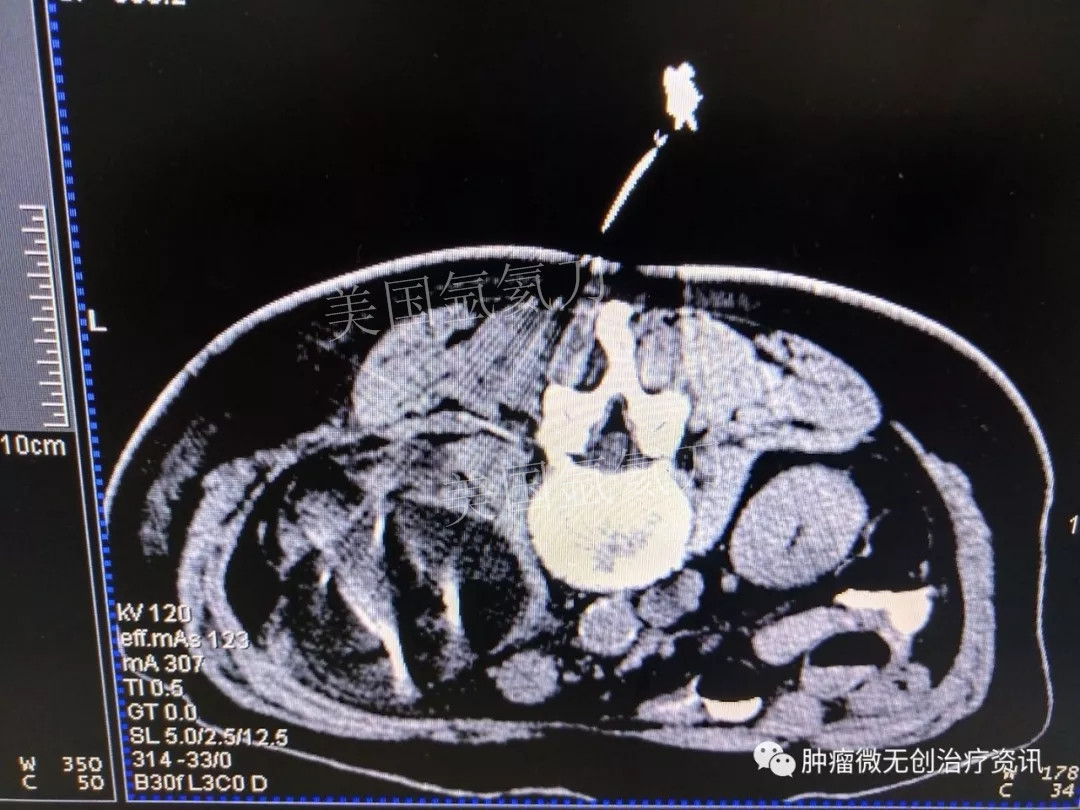

腹膜后脂肪肉瘤氩氦刀冷冻消融治疗——中国人民解放军第307医院

66岁女性患者,因腹膜后脂肪肉瘤,入住于中国人民解放军第307医院肿瘤微创治疗科。结合患者情况,行氩氦刀冷冻消融治疗。